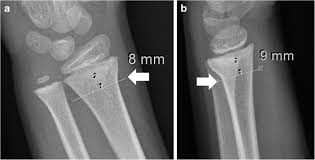

Radiograph Of Torus Fracture Of Distal Radius Anterior Posterior And Download Scientific Diagram

Radiograph Of Torus Fracture Of Distal Radius Anterior Posterior And Download Scientific Diagram from www.researchgate.net